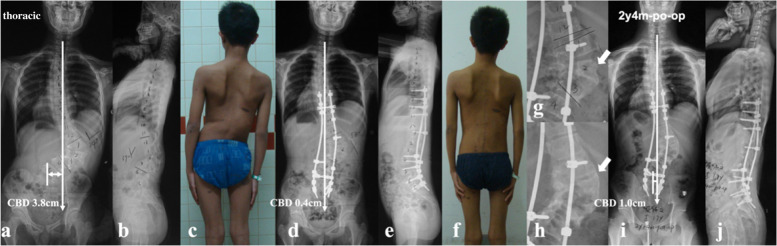

All the recruited patients were stratified according to the location of dystrophic curve apex: thoracic group, 4 cases (26.7%) (Fig. 1a, b); thoracolumbar/lumbar group, 11 cases (73.3%) (Fig. 1c, d). Among them, 1 patient in thoracic group and 3 patients in thoracolumbar/lumbar group received staged surgery with combined posterior-anterior or anterior- posterior approach (Table 1), while the rest 11 patients (73.3%) underwent posterior-only spinal instrumentation and fusion. Supplementary anterior fusion utilizing structural fibular allograft (2 patients) (Figs. 2, 8) or autogenous rib grafts (1 patient) (Fig. 3) was applied when the pedicle screw density in the apical region was distinctively low due to pedicle dystrophy disabling screw insertion. Stage 1 anterior release involving intervertebral disc resection and autogenous rib grafting was performed in 1 patient of thoracolumbar/lumbar group, followed by skull-femoral traction for 2 weeks and subsequent stage 2 posterior spinal correction and fusion.

Based on the lessons learned from this rare case series, tips for implementing better correction maneuvers when treating this particular patient group were summarized. Rod insertion with derotation and compression maneuvers firstly on the convex side was well known to be beneficial for correction of main curve. However, over correction was easy to occur with simultaneous reverse tilt and translation of UIV to the convex side, resulting in inadvertent aggravation of CCI, particularly for those with thoracolumbar/lumbar apex and vertical proximal hemi-curve. Contrarily, if the rod was firstly inserted on the concave side using translation rather than derotation and cantilever as main correction technique, the risk of over correction of main curve was relatively small, reducing the risk of CCI aggravation. The position of UIV, being represented by its tilt and translation, was of valuable information in evaluating whether or not the coronal rebalance failed intraoperatively. If the UIV tilt and translate to convex side, fine-tuning using concave compression/convex distraction and coronal rod bending in upper hemi-curve region were beneficial to increase the coronal compensation (Fig. 7). Finally, a vertical morphology of instrumentation being confirmed by intraoperative fluoroscopy was essential for reliable coronal realignment.

The follow-up data revealed that patients in the imbalanced group experienced spontaneous improvement of CCI over time (Ratio of CBD < 3 cm: 100%). This usually resulted in an acceptable but not satisfying coronal alignment because residual tilting of the instrumentation mass and/or junctional angulation centering around LIV existed (Fig. 8), and might result in implant failure (Fig. 5). Both distal compensation (decreased tilting of the instrumentation mass and LIV to the convex side) and proximal compensation (increased UIV disc angle) accounted for such coronal rebalance, and our data was suggestive that the distal compensation was the mainstay compensative mechanism. This was in line with Bao’s previous finding that LIV at L4 or higher was correlated to a higher chance of spontaneous coronal rebalance [ref. 7].